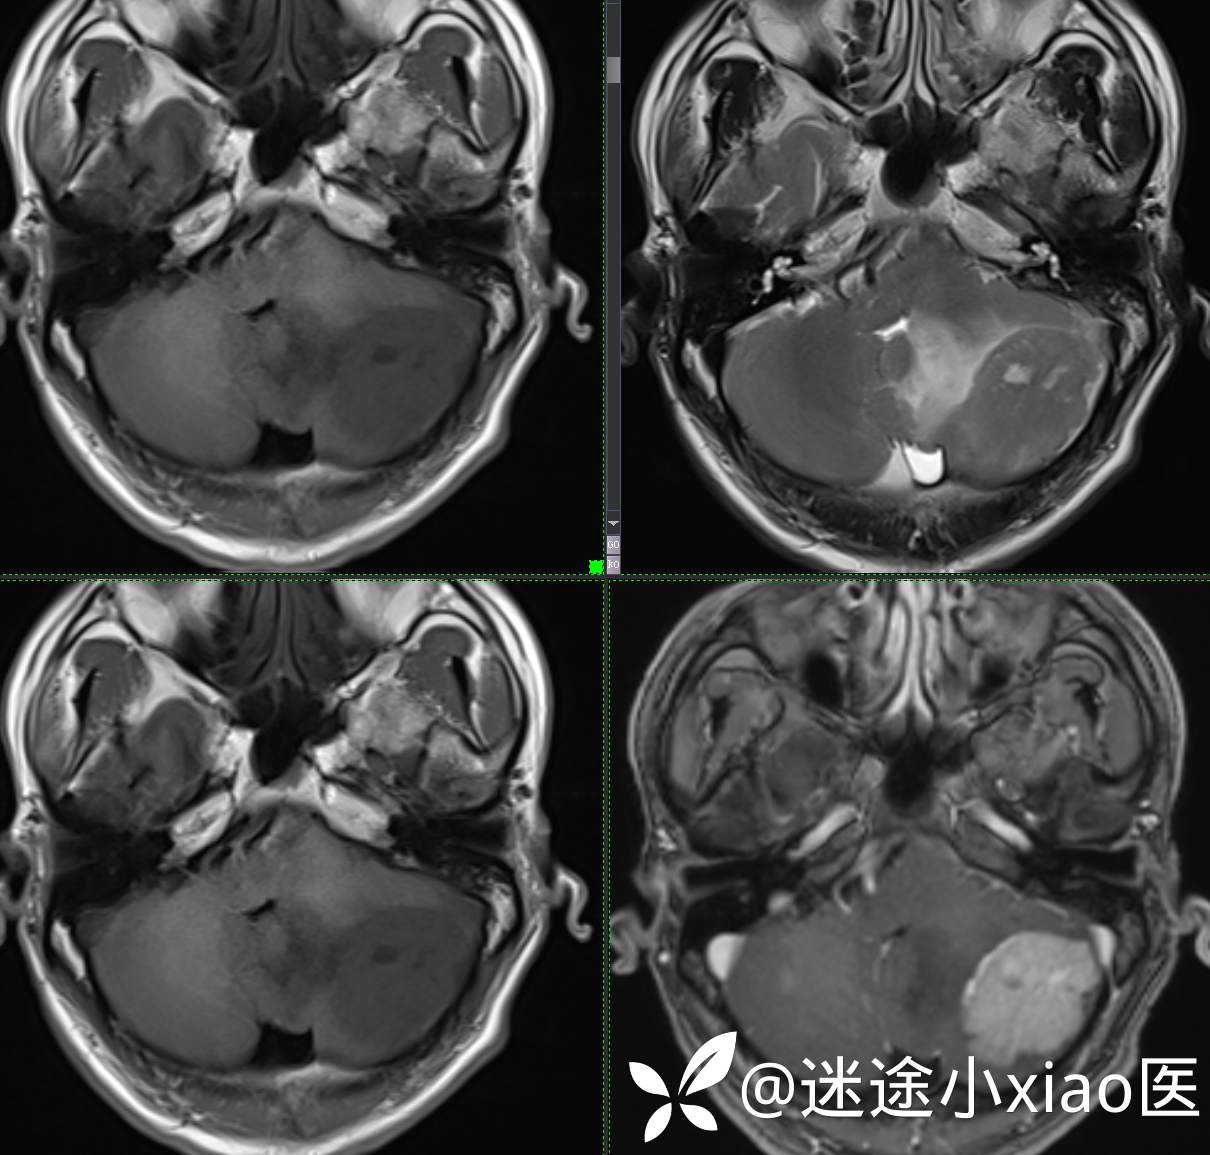

头颈组15:男,62岁,左侧小脑半球占位,原发?转移?是否有意外?

主 诉: 头晕、恶心呕吐半月余。

现病史: 患者半月前无明显诱因下明显头晕,伴恶心呕吐,无意识丧失、无智力明显下降,无视物模糊,无耳鼻腔出血,无四肢抽搐、畸形,无胸闷气促、呼吸困难。

既往:膀胱癌手术史。